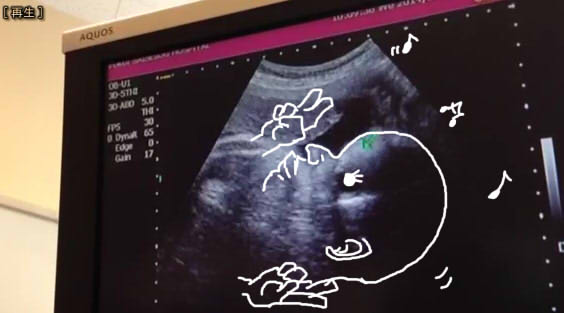

めっちゃ俊也さんやんけ!!!!!!!!!!!!!!!!!

は!????????????

俊也さんのお父さんと、俊也さんのまんまのシュルエット・・・・oh・・・・・・

ついこないだまでスヤァみたいなアザラシみたいだったのに

※ピースはしてません2700gです

ワタシ、コダワルカラ!!

だから、画面スマホでムービーで撮って、パソコンで好きなとこを画像で取ってってした方が

一々スキャンもしなくてもいいし好きなようにできるって!!!!!!!